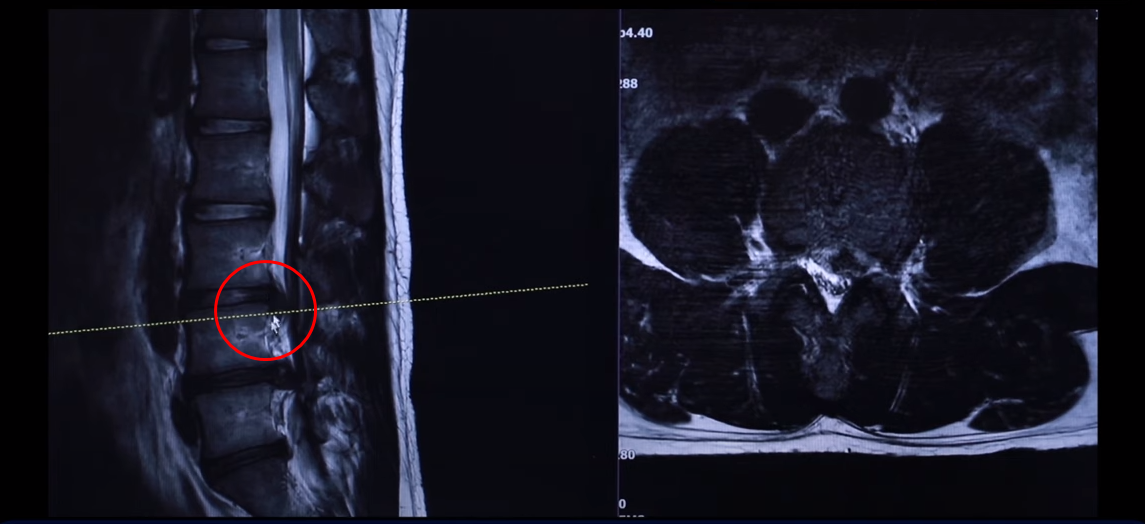

그 다음 마디 4번, 5번 보시면 보시다시피 아예 신경이 거의 보이지 않을 정도로 많이 밀려나왔습니다. 이렇게 심하게 파열된 경우를 보는 건 참 드뭅니다. 거의 신경이 보이지 않을 정도로, 오른쪽에 약간 하얀 부분이 남아 있습니다. 그래서 이 환자분 증상이 왼쪽 다리 증상입니다.

왼쪽 다리에 참을 수 없을 정도로 심한 방사통이 생긴 겁니다. 이분이 디스크가 왜 터졌냐? 24살이신데 어릴 때부터 허리가 아팠습니다. 고등학교 때부터 오랫동안 허리가 아팠기 때문에 나이에 맞지 않게 세 마디가 벌써 퇴행돼 있죠. 군대 때도 아팠고 최근에 중량 스쿼트, 웨이트 트레이닝 하다가 디스크가 터지게 됩니다. 웨이트 트레이닝 하다가 다리가 이상한 걸 느껴서 병원에 가서 MRI를 찍어 보니까 이렇게 심하게 터져 있습니다. 보통 이렇게 심하게 터져 있으면 어느 병원을 가든 정형외과나 신경외과에서 수술을 해야 된다 이런 얘기를 들을 가능성이 있습니다.